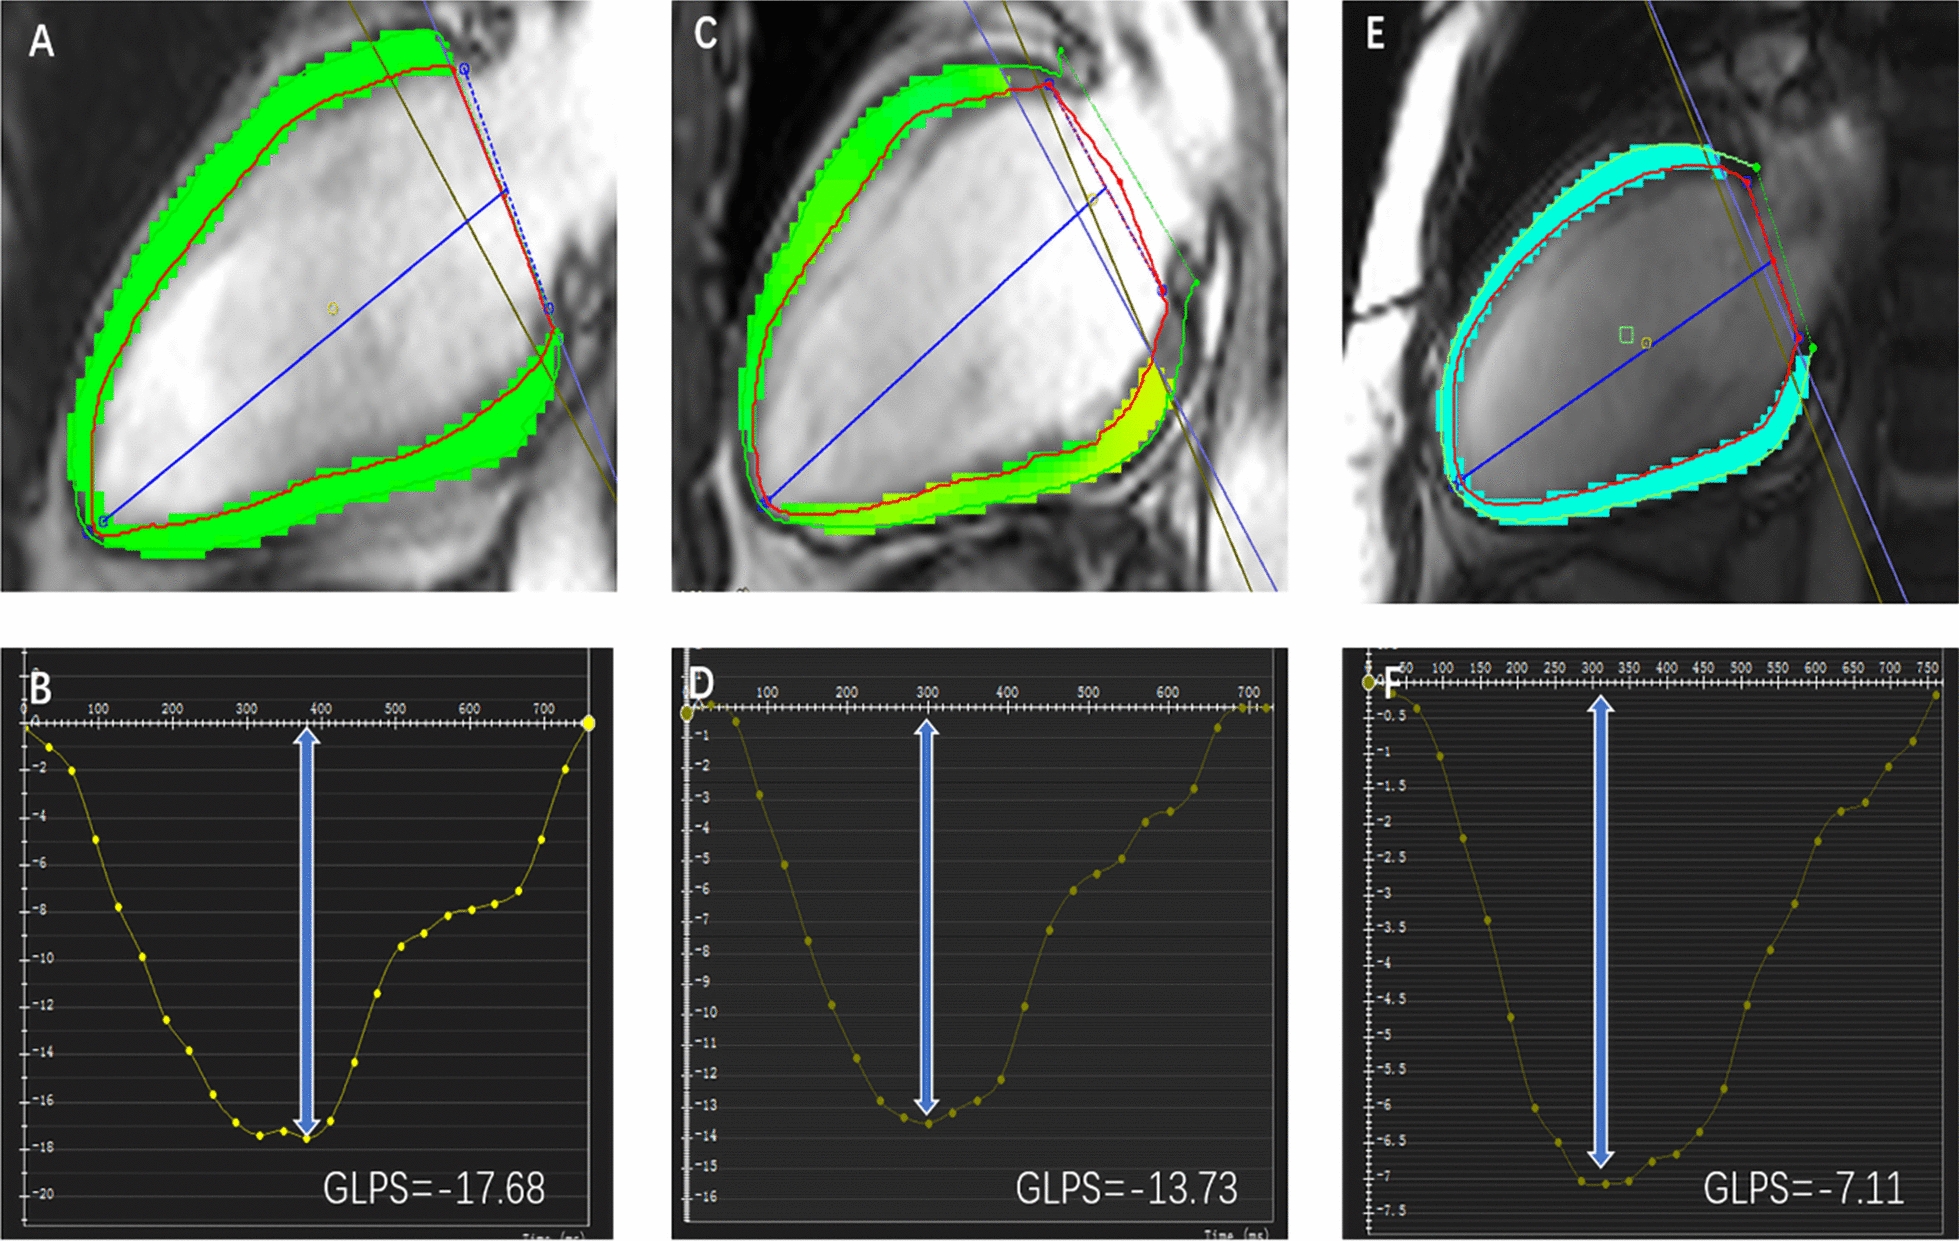

Among the three groups, all three directions of LV global peak strain progressively and significantly worsened from controls, through T2DM patients without anemia, to T2DM patients with anemia (radial 33.4% (29.0, 42.4) vs. 31.2% (23.6, 36.7) vs. 23.2% (16.2, 36.4); circumferential −21.1% ± 3.0 vs. −18.8% ± 4.3 vs. −15.6% ± 5.3; longitudinal −13.2% ± 2.5 vs. −11.5% ± 4.3 vs. −8.9% ± 4.4; all p < 0.001. Figure 2). Figure 3 shows representative CMR-derived longitudinal peak strain curves in a normal control, a T2DM patient without anemia, and a T2DM patient with anemia. For peak diastolic strain rate (PDSR), radial and circumferential PDSR progressively and significantly worsened from controls to T2DM patients without anemia to T2DM patients with anemia (all p < 0.001). The longitudinal PDSR of T2DM patients with anemia was significantly lower than that of the other two groups, while the other two groups showed no significant difference (p < 0.001). For peak systolic strain rate (PSSR), there were no significant differences between the T2DM with and without anemia groups in all three directions, while the control group had a higher PSSR than the two T2DM groups except for longitudinal PSSR (all p < 0.05, Table 2).

Fig. 3.

Representative CMR pseudocolor images at the end-diastole and CMR- derived peak strain curves. A, C, E: LV pseudocolor images in the vertical 2—chamber long‑axis; B, D, F: LV global peak strain curve in the longitudinal direction; A, B: a patient of control group; C, D: a T2DM patient without anemia; E, F: a T2DM patient with anemia. GLPS, global longitudinal peak strain